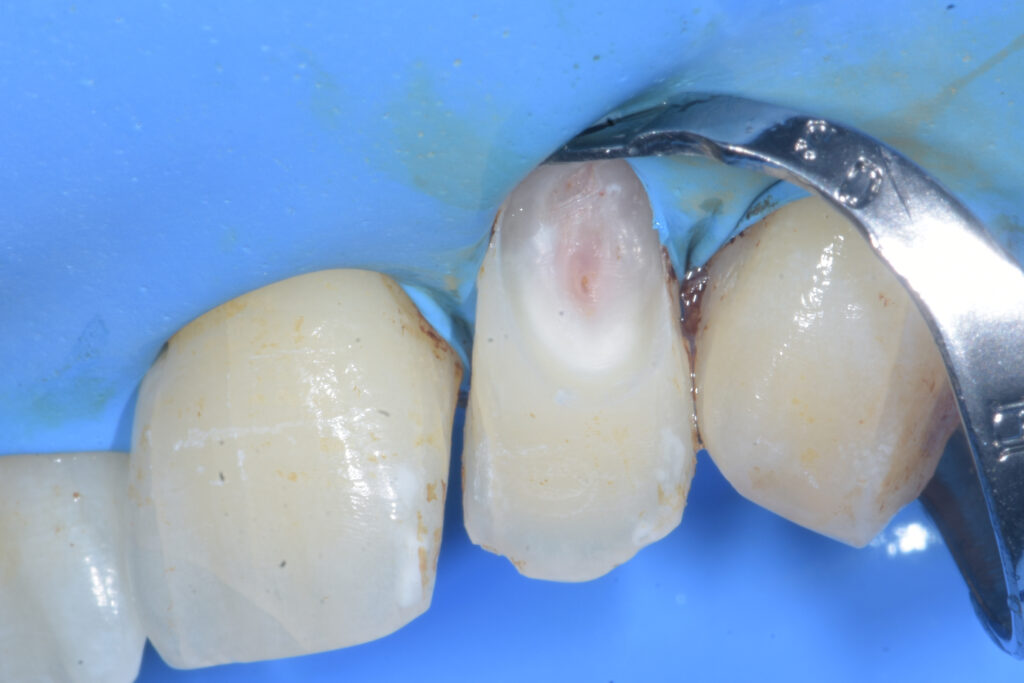

Al termine di quest’ultima fase, l’elemento viene isolato con diga di gomma mediante la tecnica dell’uncino accessorio (Figura 4).

Riassorbimento cervicale esterno